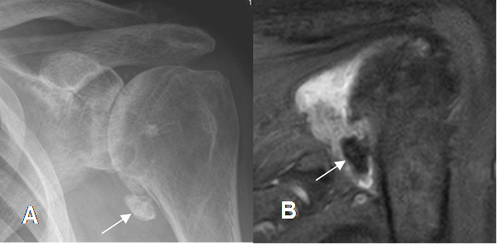

Presencia de osteofitos, disminución no uniforme del espacio articular, esclerosis ósea y quistes subcondrales. El compromiso es asimétrico. (Fig 161 A, 161 B y 161 C).

Fig 161 A. Artropatía degenerativa.

A: Rx AP. Cambios degenerativos con pérdida del espacio, formación de

osteofitos inferiores (Flecha delgada) y quistes subcondrales. (Flechas gruesas).